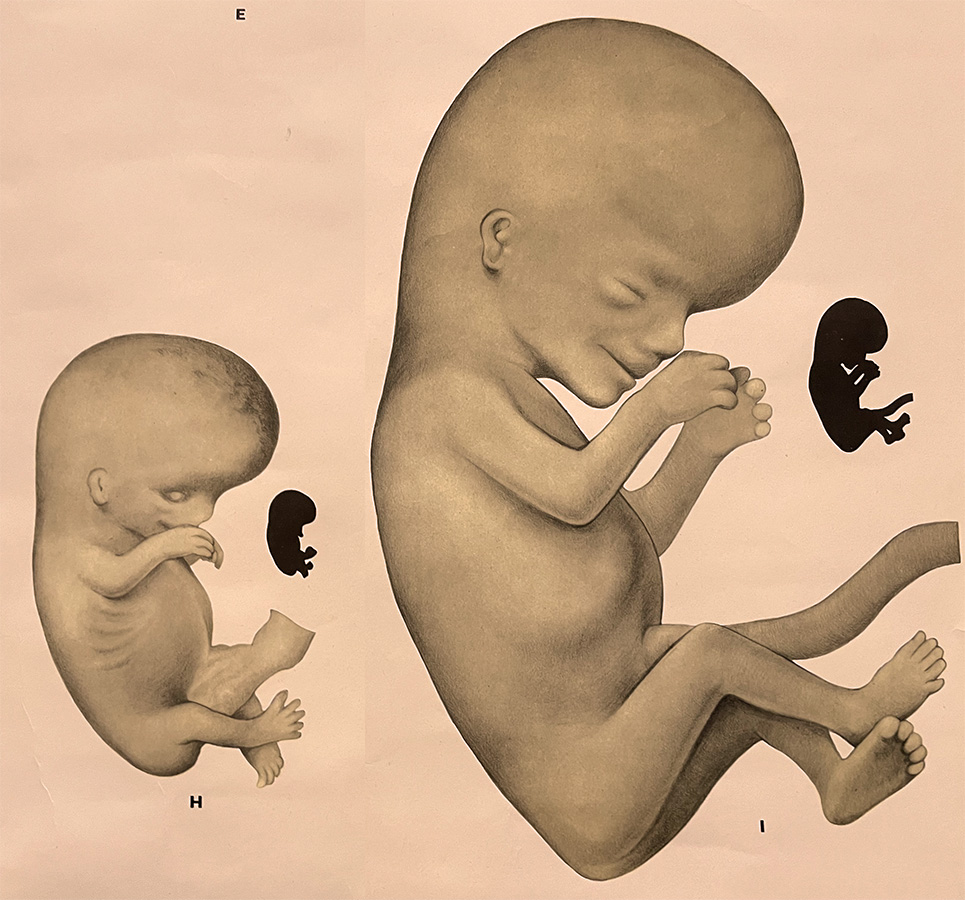

Early diagnosis of increased NT triggers the SMART NT protocol. Detection of lethal anomalies, such as acrania or body stalk anomaly, serves as an exclusion criterion for NIPT.

A specialist scan aimed at excluding structural anomalies associated with high NT, particularly heart defects. It also assesses changes in NT over time, which provide important prognostic information.